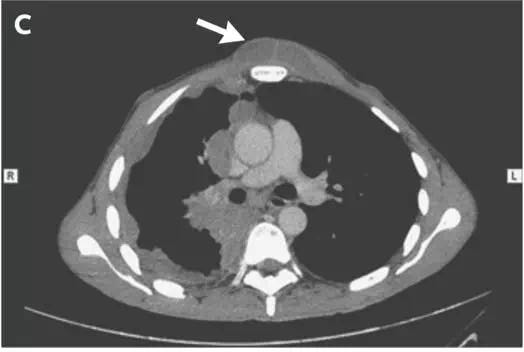

一名40岁男性患者因发热、体重减轻、呼吸困难及咳嗽3个月就诊。体格检查显示前胸壁有一压痛突出肿物,右侧乳头内下方有一小的溃疡性病变(图A)。CT扫描显示胸腔积液(图B)穿透胸壁(图C,箭头),并伴有骨骼破坏。